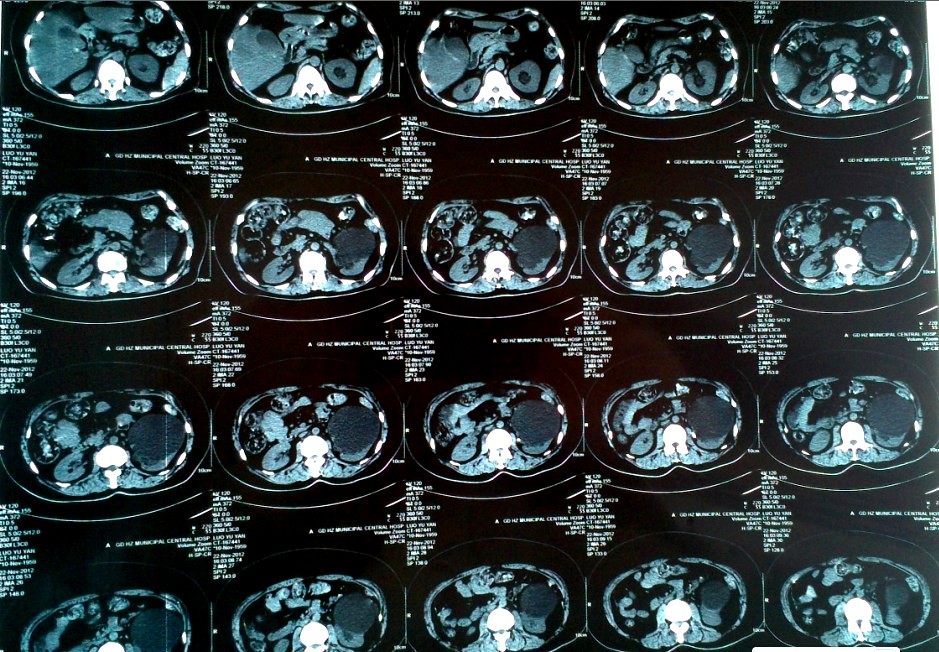

圖片 CT片顯示左腎囊腫位于腎中極緊貼并擠壓腹腔

患者駱某,女性,53歲,因“左側(cè)腰腹部疼痛10天余”來(lái)我院。就診之前曾在多家大型綜合醫(yī)院就診,均診斷為“左腎巨大囊腫,左輸尿管上段結(jié)石并左腎積水”,按照一般治療原則,行腹腔鏡手術(shù)很容易就可以將腎下極的囊腫摘除,是治療腎囊腫的首選術(shù)式。但是該患者囊腫的位置偏偏不在腎下極而且緊貼腹腔,加上合并輸尿管結(jié)石、腎積水無(wú)疑給手術(shù)操作帶來(lái)了極大的難度及迷惑性,所以幾家大醫(yī)院均建議開放手術(shù),患者及家屬對(duì)于開刀手術(shù)極不贊同,為此抱著試試看的態(tài)度來(lái)到我院。

我院自2007年以來(lái)在本地區(qū)率先開展各類泌尿腹腔鏡手術(shù)至今已超過300例,其中包括一大批更復(fù)雜更難做的復(fù)雜性手術(shù)我們均順利完成,積累了一定的經(jīng)驗(yàn),已經(jīng)掌握了較為嫻熟的操作技巧,所以,當(dāng)泌尿外科楊偉忠主任在仔細(xì)詢問病史、閱過CT和腎靜脈造影片后斬釘截鐵的對(duì)患者及家屬說(shuō):“放心,我們可以微創(chuàng)手術(shù)幫你解決,不用開刀!”

201211289時(shí)20分在手術(shù)室全麻下先利用輸尿管鏡為患者解除了左側(cè)輸尿管結(jié)石及腎積水,然后利用三個(gè)“小洞”的腹腔鏡手術(shù)將復(fù)雜而又迷惑的腎囊腫徹底切除。為什么說(shuō)是迷惑的腎囊腫呢?因?yàn)榛颊咦筝斈蚬苌隙谓Y(jié)石合并了腎積水,很有可能是腎盞憩室,那么假如判斷失誤將腎盞憩室或積水腎皮質(zhì)切除掉,后果可就不堪設(shè)想了,瘺尿、腹膜后感染等并發(fā)癥就會(huì)接踵而至??上驳氖切g(shù)后病理結(jié)果證實(shí)就是腎囊腫。